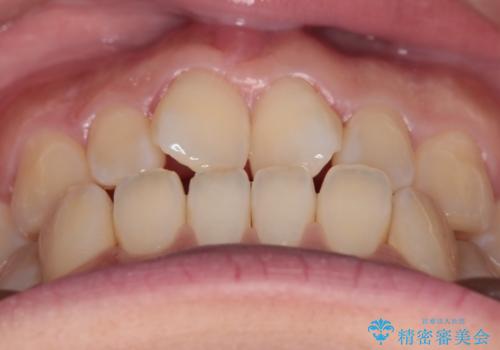

- 上の前歯の捻れを主訴に来院されました。

前歯の捻れとがたつきを改善するために、IPR(歯と歯の間を削る処置)と歯列拡大をすることで歯並びを整えていく治療計画を立てました。